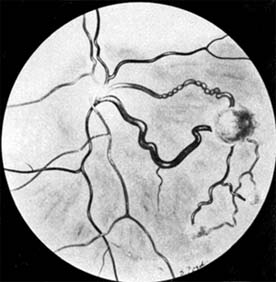

Figure 10-33

Figure 10-33: Endophytic retinoblastoma.

Retinoblastomas may exhibit outward (exophytic) or inward (endophytic) growth-either or both. The latter then extend into the vitreous (Figure 10-33). Both types gradually fill the eye and extend through the optic nerve to the brain and, less commonly, along the emissary vessels and nerves in the sclera to the orbital tissues. Occasionally, they grow diffusely in the retina, discharging malignant cells into the vitreous or anterior chamber, thereby producing a pseudoinflammatory process and mimicking retinitis, vitritis, uveitis, or endophthalmitis. Microscopically, most retinoblastomas are composed of small, closely packed, round or polygonal cells with large, darkly staining nuclei and scanty cytoplasm. They sometimes form characteristic Flexner-Wintersteiner rosettes, which are indicative of photoreceptor differentiation. Degenerative changes are frequent, accompanied by necrosis and calcification. A few will spontaneously resolve.